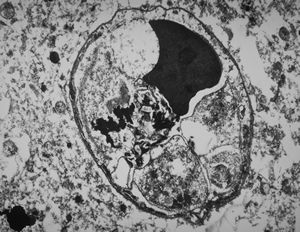

F,3y. | toxoplasmosis